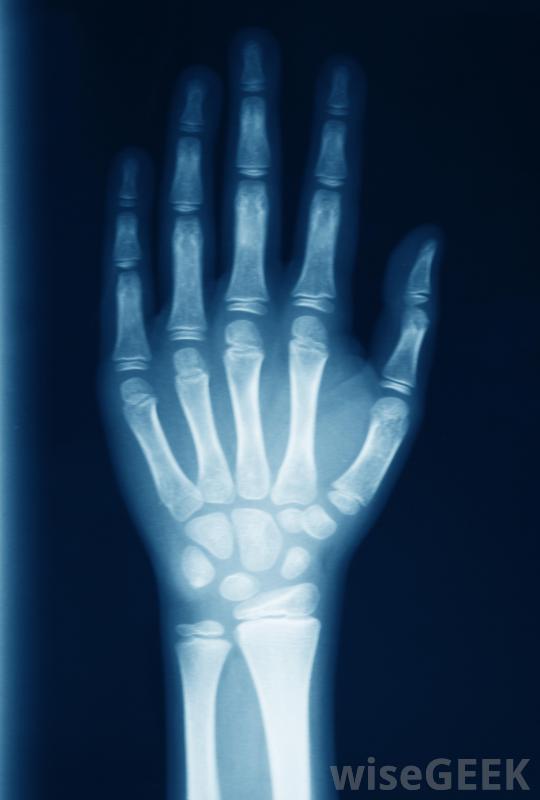

医生通常会拍x光片,以确定拇指脱臼的最佳治疗方法。许多医生还建议在脱臼的拇指。要做到这一点,在拇指下面的手掌上敷一块冰袋。如果没有现成的冰袋,任何冷的或冷冻的东西都可以,比如一袋冷冻蔬菜这样可以减轻疼痛,减轻患处的肿胀。

拇指脱臼的人应尽量避免打字用夹板夹住大拇指时,尽可能使其保持原来的位置。如果没有可用的拇指或手指夹板,可用直的、平的、硬的棍子,例如冰棍,捏一下就可以了。先把木棒轻轻地放在手掌上,跟着大拇指。然后你可以把夹板粘在拇指上,先把拇指尖粘到夹板上。然后用胶带把夹板底部粘到拇指关节上,最后包裹拇指,夹板,手上用绷带或纱布即使你认为脱臼并不严重而且会自行愈合,强烈建议立即就医,以防止进一步、更永久性的损伤。当你为拇指脱臼寻求治疗时,医生可能会做的第一件事就是拍x光片,这样他就能看到损伤的程度,包括你有没有骨折。脱位可以是简单的,也可以是复杂的。如果是简单的拇指脱位,韧带通常会被拉伸或轻微撕裂。这种脱臼的拇指被认为是最容易治疗的,通常只需要医生将拇指移回关节。很多时候,拇指需要固定,通常用石膏固定大约三周。之后手指慢慢地移动会回来。复杂的拇指脱位通常会更严重一些,因为至少有一条韧带完全撕裂。大多数情况下,修复损伤需要手术。手术后,拇指通常需要固定长达6周。有些患者可能还需要进行物理治疗以恢复整个活动范围。

医生可以确定拇指是否脱臼,扭伤或折断。